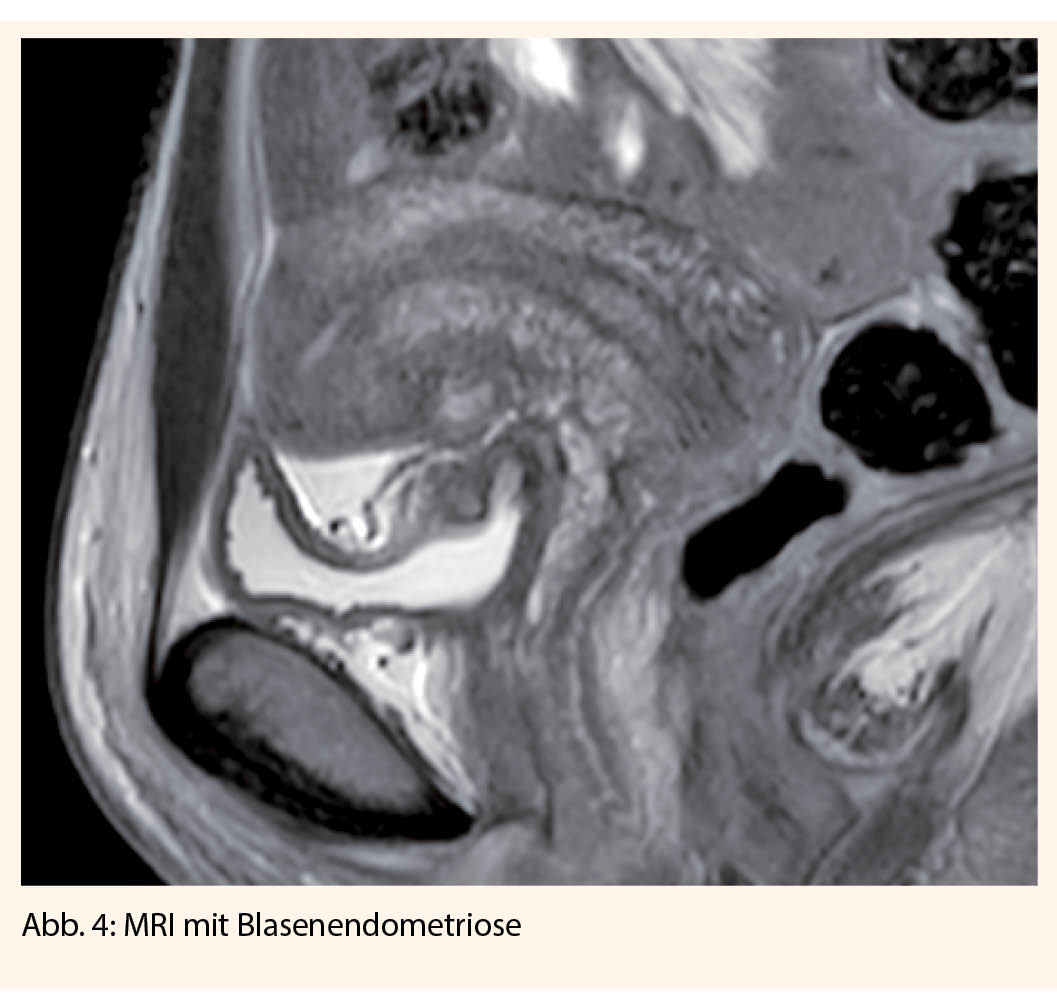

Mittels Ultraschall können durch den erfahrenen Untersucher auch tiefinfiltrierende Herde im Bereich des Septum rektovaginale, der Sakrouterinbänder, der Blase und des Darms dargestellt werden. Bei Hinweisen für eine tiefinfiltrierende Endometriose mit Verdacht auf Darmbeteiligung, Beteiligung der Blase, Ureteren, und auch bei extrapelviner tiefinfiltrierender Endometriose, sollten noch weitere Untersuchungen durchgeführt werden:

Bei urologischer Beteiligung der Endometriose (Blase 85%, Ureter 9%) kann ein operativer Eingriff zur Reduktion der Symptomatik und Verbesserung der Schwangerschaftsrate sinnvoll sein. Je nach Infiltrationstiefe muss ein vesikales Shaving oder auch eine Blasenteilresektion durchgeführt werden. Eine alleinige zystoskopische Resektion reicht nicht aus, da die Herde immer transmural gelegen sind. Bezüglich des Ureters können die Eingriffe, je nach Ausdehnung, von einer Ureterolyse, einer Uretersegmentresektion bis hin zu einer Neuimplantation variieren (19).